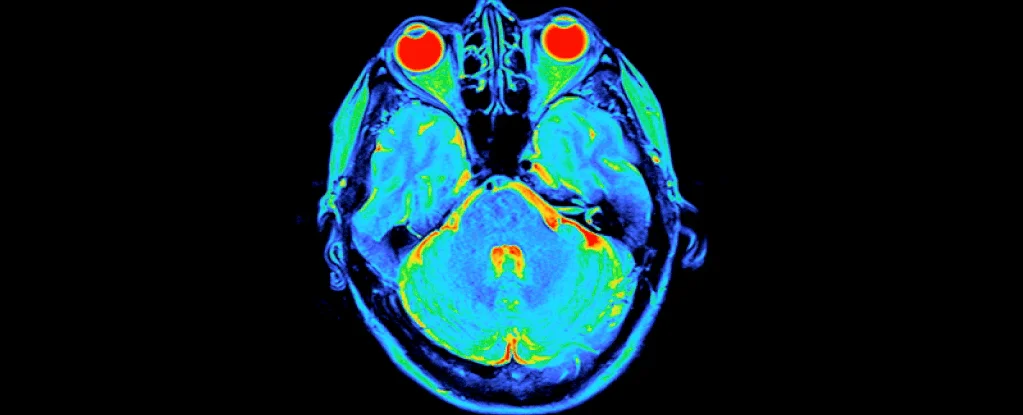

Psychedelic Users Show Unique Brain Responses to Self-Thoughts

A study comparing regular psychedelic users and non-users found differences in brain activity during self-reflection tasks, with users showing weaker activation in regions associated with self-processing, though results varied across datasets and may be influenced by lifestyle factors. The research highlights potential long-term effects of psychedelics on brain function related to self-related thoughts, but causality remains unclear.